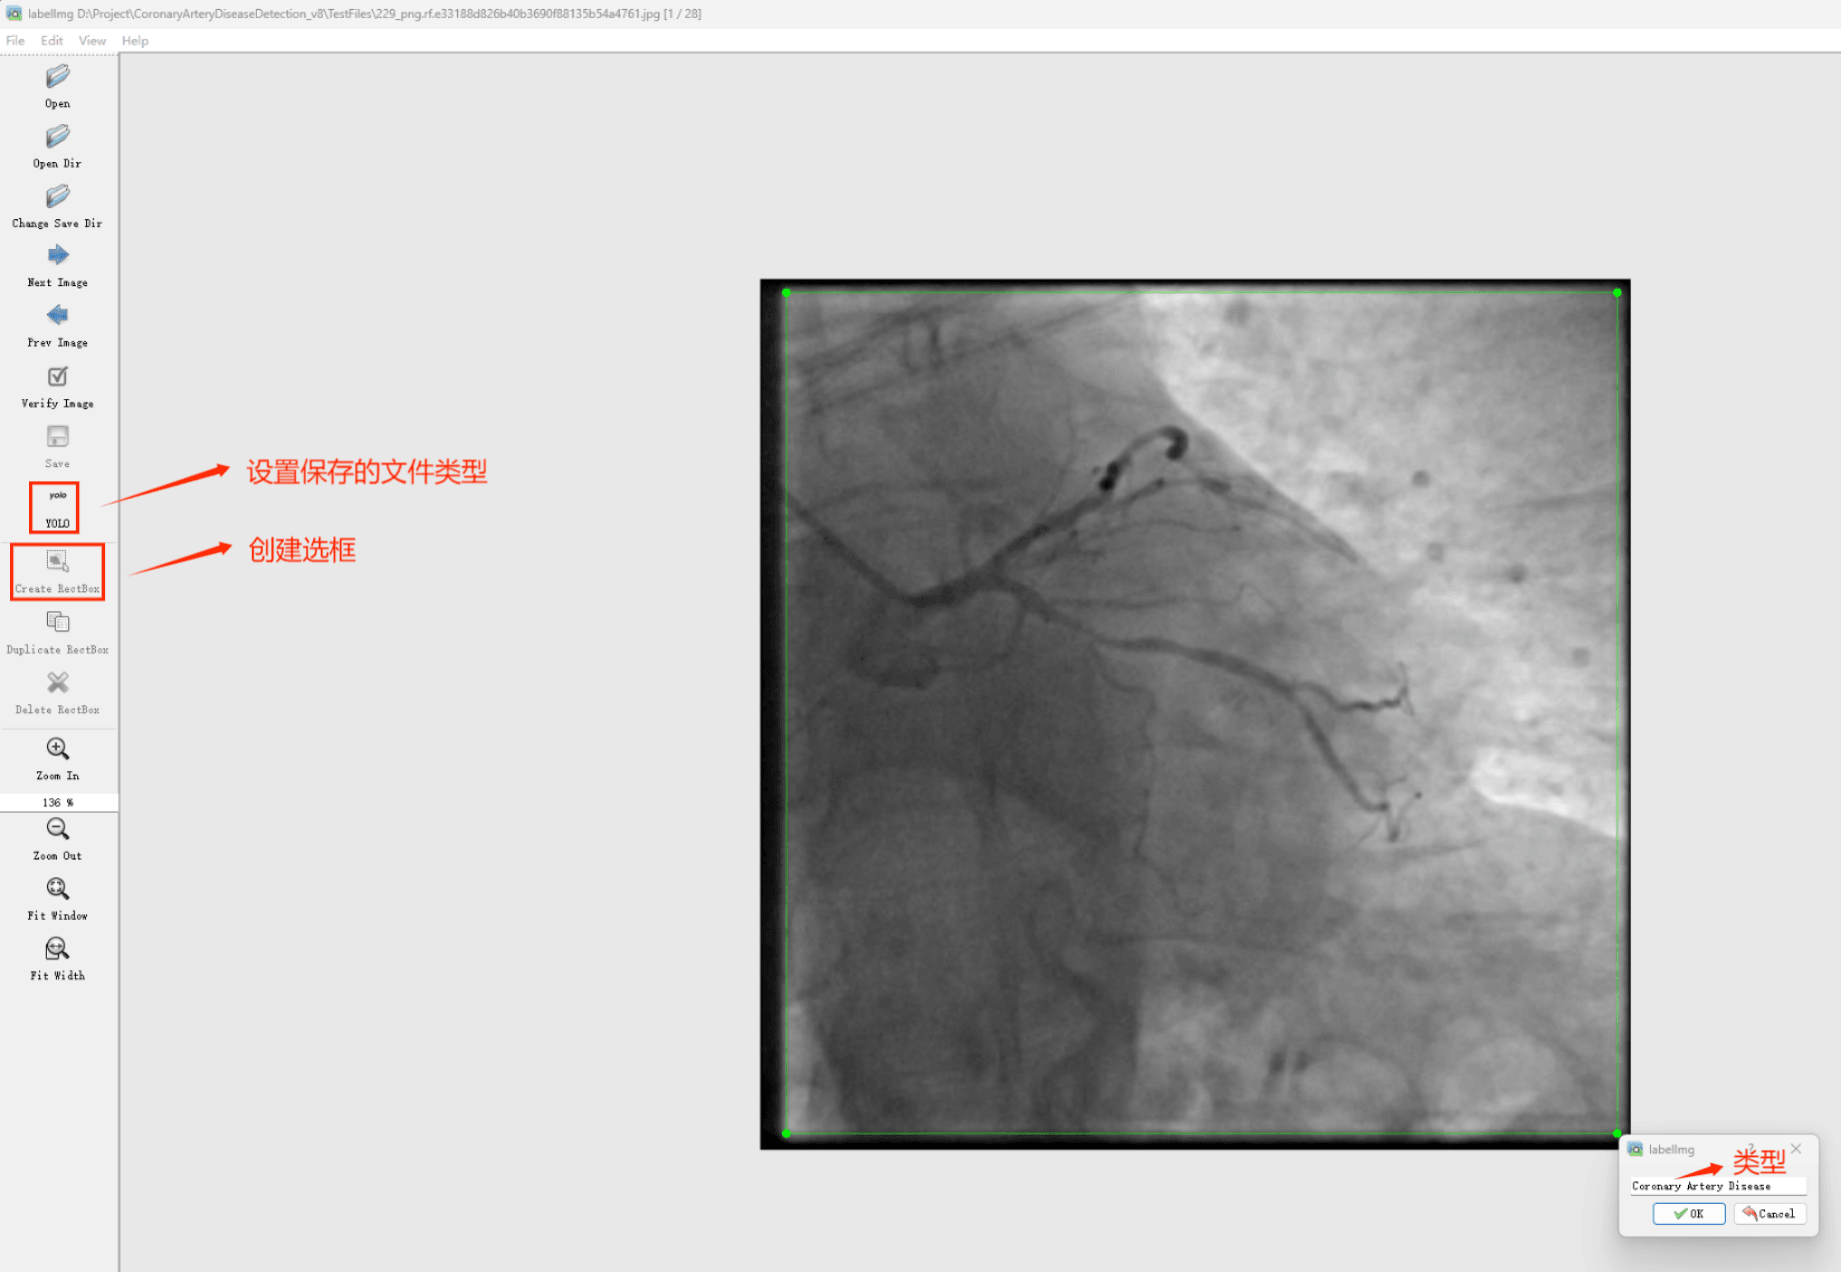

Tipps:通过搜集关于数据集为各种各样的冠状动脉疾病相关图像,并使用Labelimg标注工具对每张图片进行标注,分1检测类别,是’冠状动脉疾病’。

目标检测标注工具

(1)labelimg:开源的图像标注工具,标签可用于分类和目标检测,它是用python写的,并使用Qt作为其图形界面,简单好用(虽然是英文版的)。其注释以 PASCAL VOC格式保存为XML文件,这是ImageNet使用的格式。此外,它还支持 COCO数据集格式。

初识labelimg

打开后,我们自己设置一下

在View中勾选Auto Save mode

接下来我们打开需要标注的图片文件夹

并设置标注文件保存的目录(上图中的Change Save Dir)

接下来就开始标注,画框,标记目标的label,然后d切换到下一张继续标注,不断重复重复。

(4)YOLO模式创建标签的样式

存放标签信息的文件的文件名为与图片名相同,内容由N行5列数据组成。

每一行代表标注的一个目标,通常包括五个数据,从左到右依次为:类别id、x_center、y_center、width、height。

其中:

–x类别id代表标注目标的类别;

–x_center和y_center代表标注框的相对中心坐标;

–xwidth和height代表标注框的相对宽和高。

注意:这里的中心点坐标、宽和高都是相对数据!!!

存放标签类别的文件的文件名为classes.txt (固定不变),用于存放创建的标签类别。

完成后可进行后续的yolo训练方面的操作。